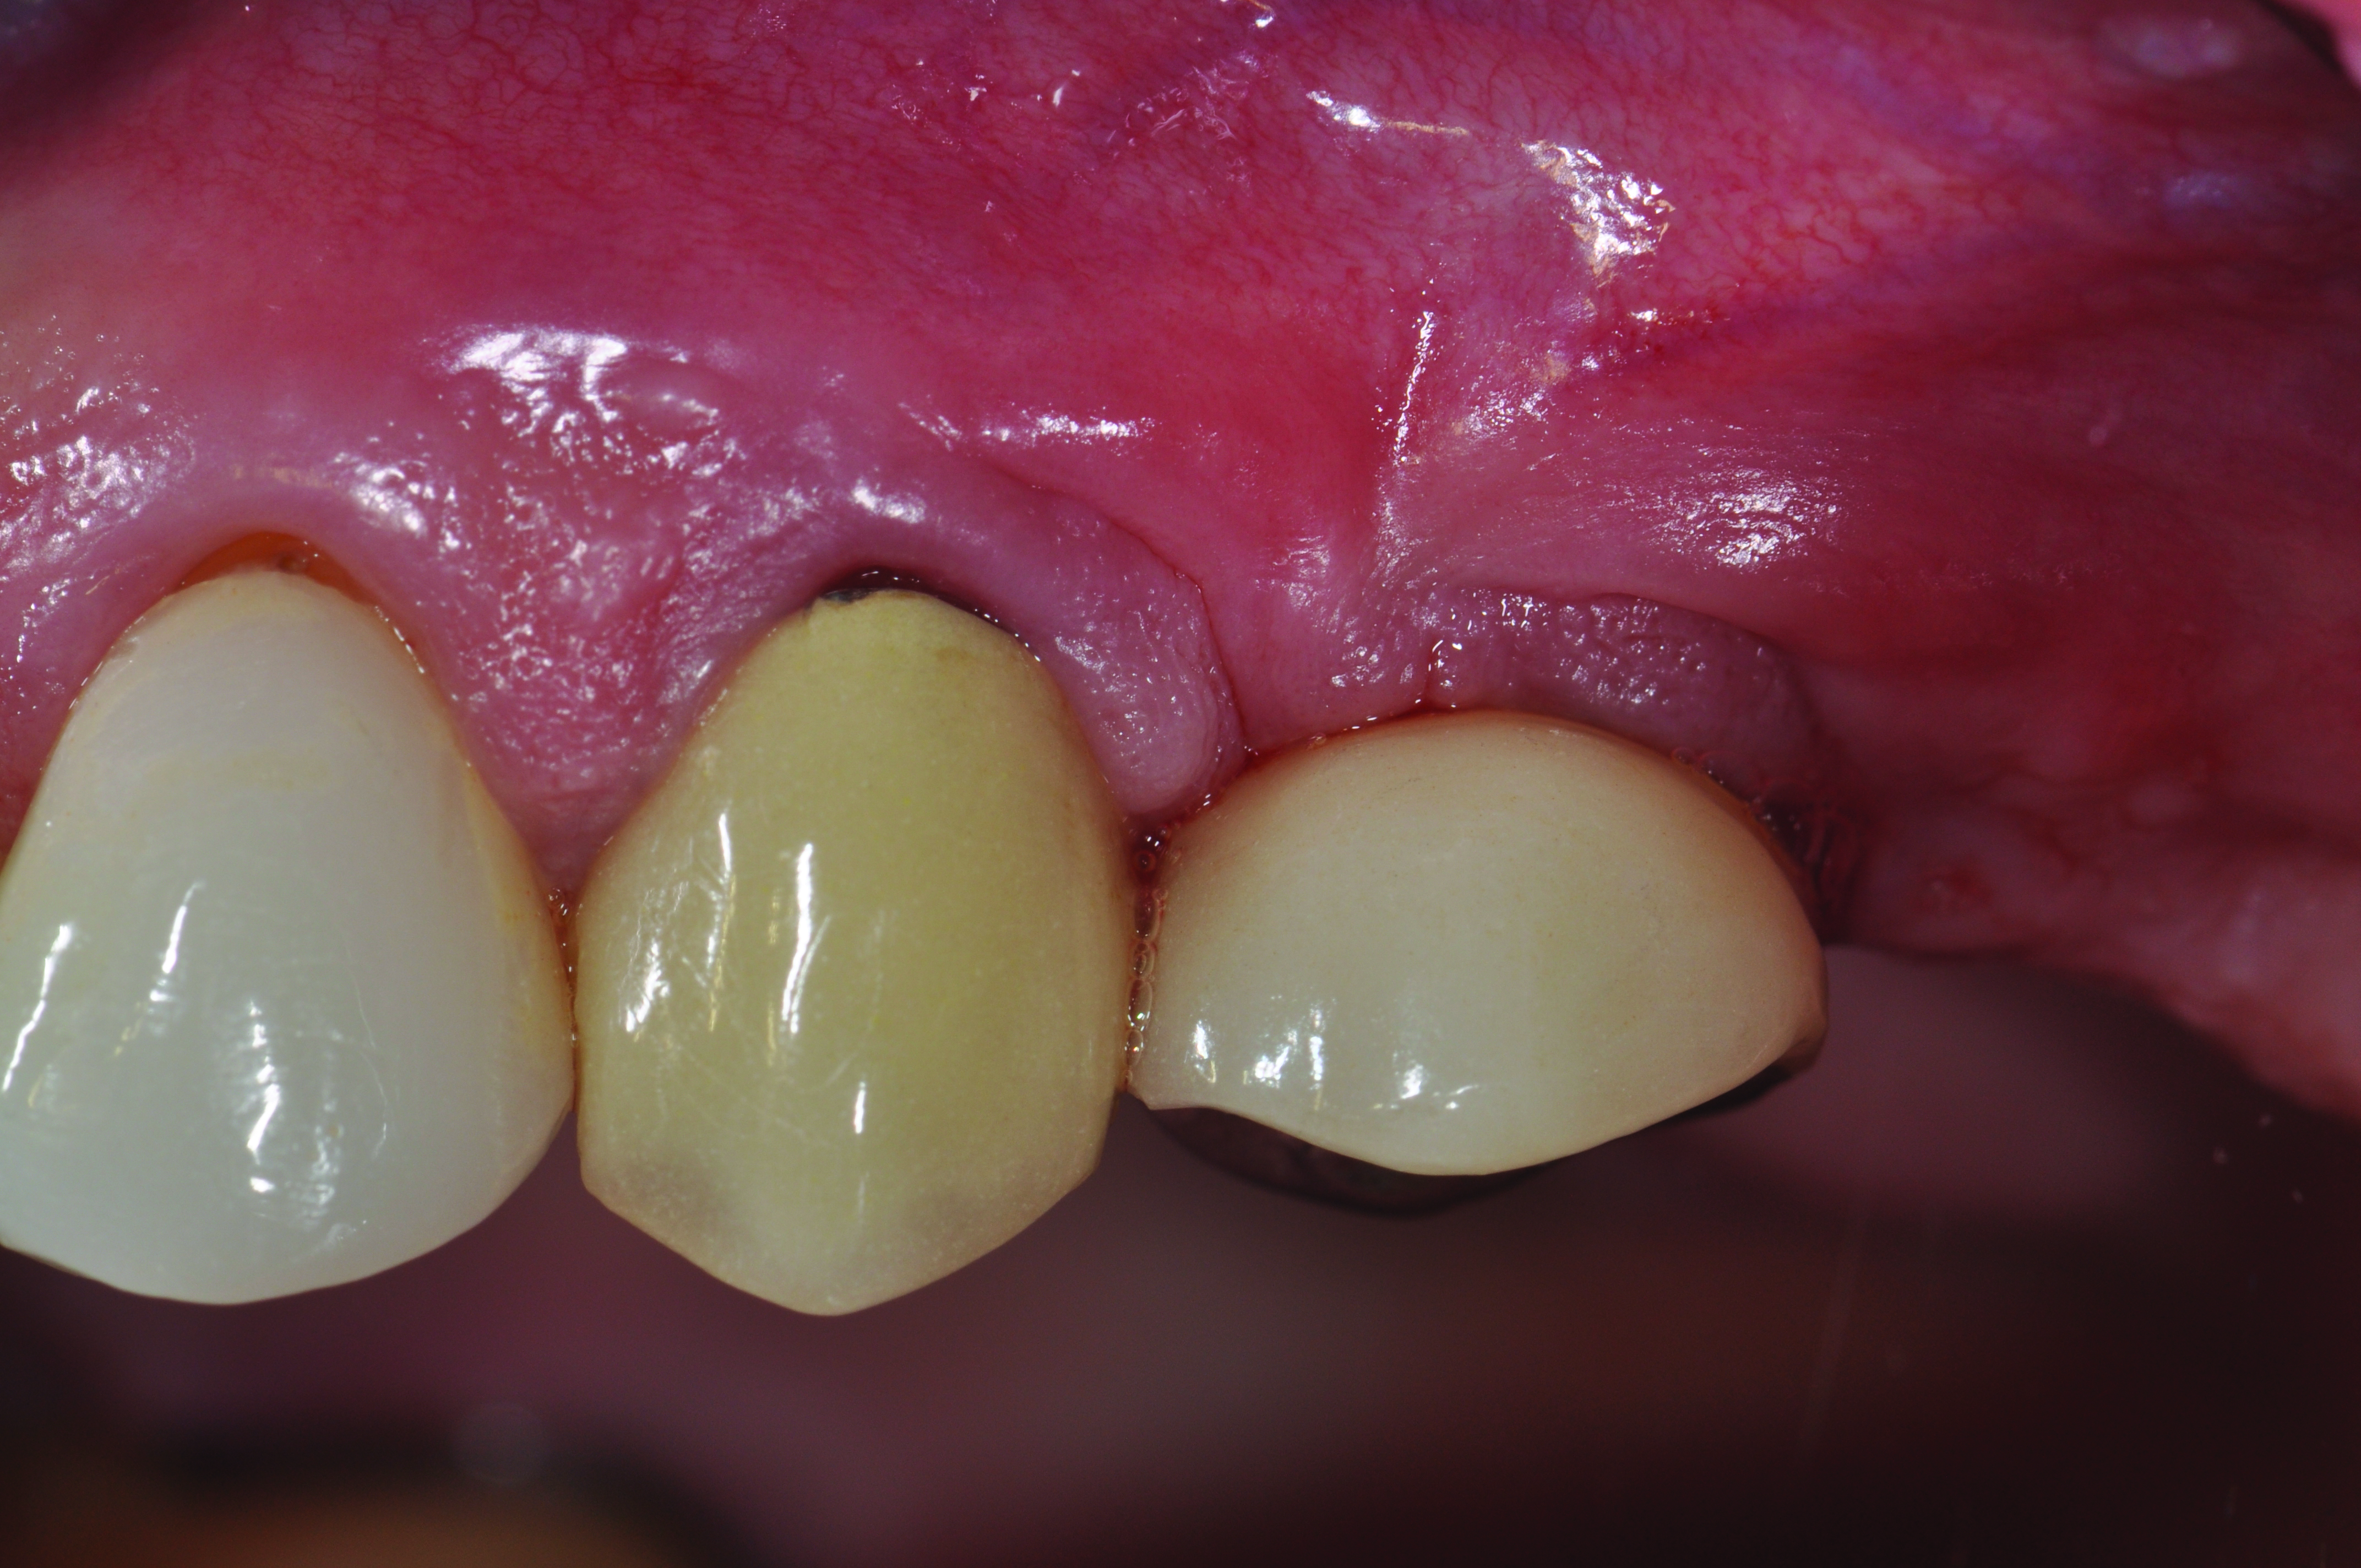

Peri-implant diseases present in two forms—peri-implant mucositis (Figure 1 and Figure 2) and peri-implantitis (Figure 3 and Figure 4). Both involve an inflammatory reaction in the tissues surrounding an implant—ie, bleeding on probing and/or suppuration; probing depths usually exceed 4 mm.1,3 However, when there is also bone loss present beyond the physiologic remodeling that may occur after implant placement, a diagnosis of peri-implantitis should be made, as this condition, when compared to mucositis, is far more serious and difficult to resolve.4

Clinical view of a maxillary left second premolar in an 73-year-old patient with a history of smoking. The tissue around the implant is quite inflamed and probes up to 8 mm with bleeding.

Figure 3